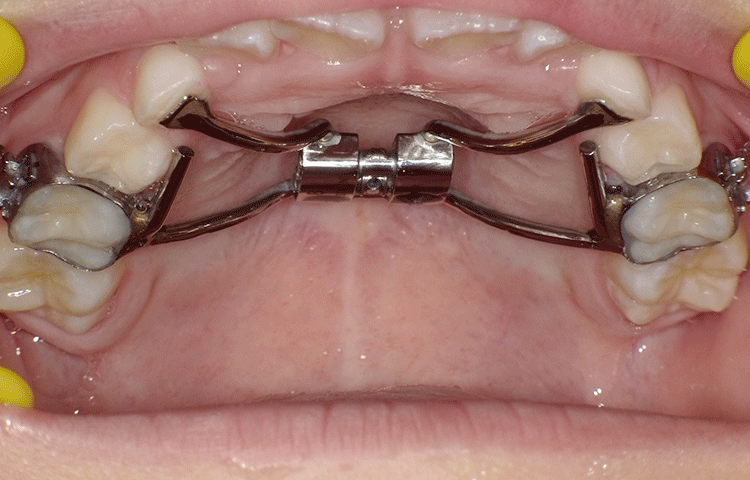

急速拡大装置

急速拡大装置とは、上顎の横幅を拡大してスペースを作るための装置です。

歯がきれいに並ぶためのスペースが足りない場合に行う矯正治療です。

一般的には上顎が成長する10歳までに使用します。

急速拡大装置は固定式で、力をかけて上顎を骨ごと広げる治療のため、装着した数日間は少し痛みを感じることがあります。

固定式装置になり、短期間に骨にアプローチできることから「急速」と呼ばれています。